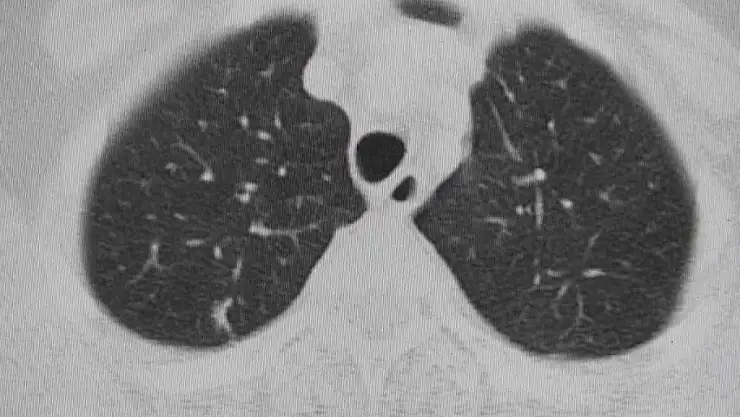

Doç. Dr. Onur Ermerak, "Akciğer kanseri, dünyada kanser nedenli ölümlerde en sık rastlanan ölüm nedenidir. Akciğer kanserinde henüz tarama aşamasına gelemedik. Amacımız o aşamaya gelip erken evrede akciğer kanserini yakalayıp o hastalığı tedavi etmeye başlamaktır. Akciğer kanserinin sigarayla ilişkili olduğunu biliyoruz. Çevre kirliliği, çeşitli kimyasallar akciğer kanserine neden olmaktadır. Maalesef geç bulgu ve şikayet verdiği için hastalar genelde geç evrede yakalanıp tedaviden yarar göremeyecek durumda bize başvuruyorlar. Sadece yüzde 15 hastada sağ kalım görülmektedir. Biz onu çok daha yüksek rakamlara çıkartıp hastalarımıza güzel günler sunmak istiyoruz. Öksürük, istenmeyen kilo kaybı, kanlı balgam, halsizlik, yorgunluk ve iştah kaybı gibi etkilerle görülmektedir. Özellikle kilo kaybı ve geçmeyen öksürük bizim için çok önemli bir bulgudur. Bu hastaların bize başvurmaları gerekir. Burada altını çizmek istediğimiz nokta, tarama programlarıyla sağ kalımda da yüzde 40'lara kadar bir artış sağlamaktayız. Tarama programı, düşük doz tomografilerle hastaları tarayıp bu hastalık daha oluşma aşamasındayken en güzel tedaviyi verip hastaların akciğer kanseri ile baş başa kalmamasını sağlıyoruz. 50 yaş üstünü geçmiş ve 15 yıl sigara tüketmiş hastaların hepsi tarama yapmalıdır. Bizim ülkemizde de aktif sigara kullanımının yanında pasif içicilik de devam ediyor ve biz bu konuyu ciddiye almalıyız. Akciğer kanserine yakalanan hastaların yüzde 90'ı sigara içmekte. Bunların arasında da yüzde 50'si sigarayı bırakmış hastalar oluyor. Hastaların merkezlere başvurup taramasını yapıp hastalığı erken evrede yakaladıktan sonra en uygun tedavilerle sağlığına kavuşmasını amaçlamaktayız. Sigara içmemek çok önemli. Sigara içilen ortamda dahi bulunmamaları çok önemli. Ve farkındalığı oluşturup en ufak bir şüphede gerekli tarama endikasyonlarıyla gidip taranmalarını öneriyoruz. Akciğer kanseri sinsi bir kanserdir, geç bulgu ve şikayet veriyor. Öncelikle sigara içmeyelim ve hastalığın taramasını mutlaka yaptıralım" dedi.